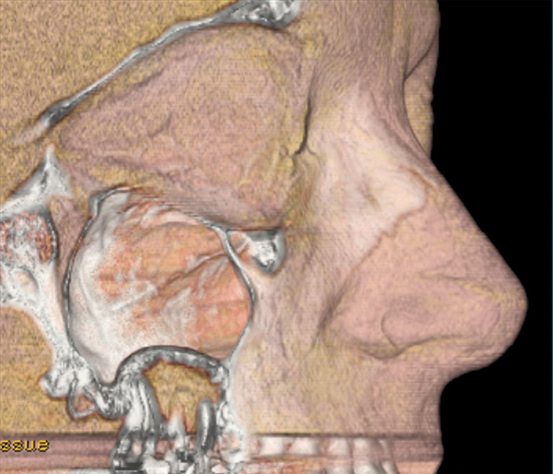

Enfin, Mai Lan Tran, implantologiste, apportera les réponses pratiques aux questions cliniques les plus concrètes : tous les sinus peuvent-ils être comblés et quelle est l’analyse préopératoire requise ? Quel matériel pour quelle technique ? Quel biomatériau et quel design implantaire choisir ?

- Étude anatomique et physiologique du sinus

- Analyse radiographique préopératoire en implantologie

- Différentes techniques d’abord sinusien : indications, contre-indications et plateau technique

- Choix du biomatériau et du design implantaire

- Appréhender l’abord sinusien en implantologie

Mieux connaître l’anatomie sinusienne et surtout les relations dento-sinusiennes ! L’omnipraticien sera capable, par exemple, de détecter les petites anomalies qui empêchent la fermeture de la communication bucco-sinusienne après extractions. Pour les confrères qui posent des implants et qui demeurent un peu frileux sur les sinus lift, il s’agira de leur apporter des clés pour une meilleure analyse des scanners, pour anticiper des anatomies sinusiennes compliquées, ou encore pour indiquer d’autres alternatives à l’élévation sinusienne./